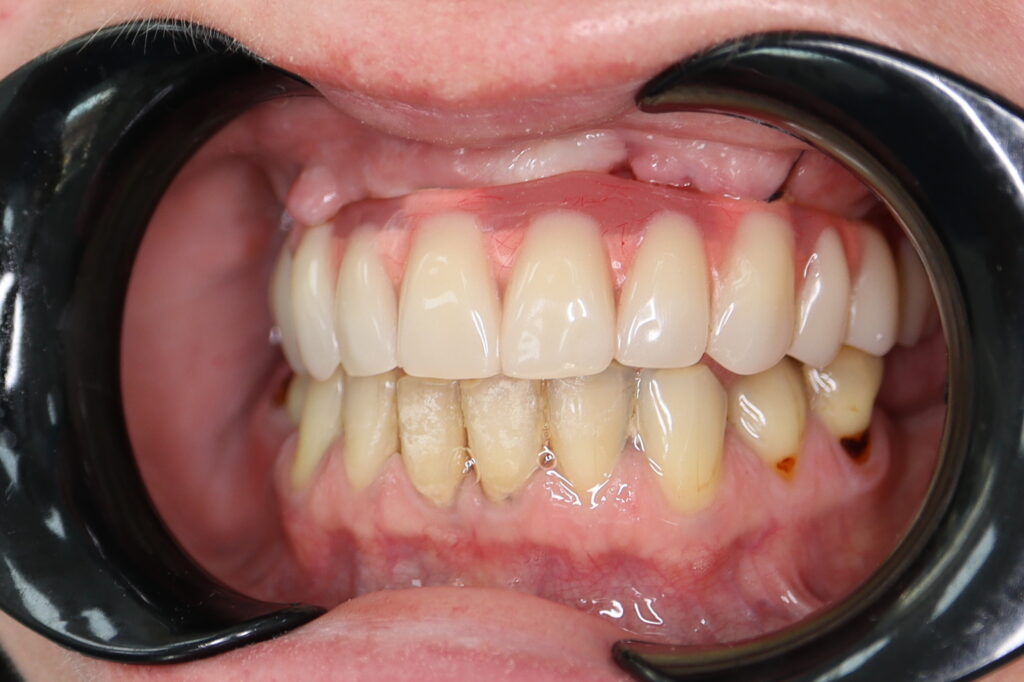

Результаты

результат тотальной имплантации